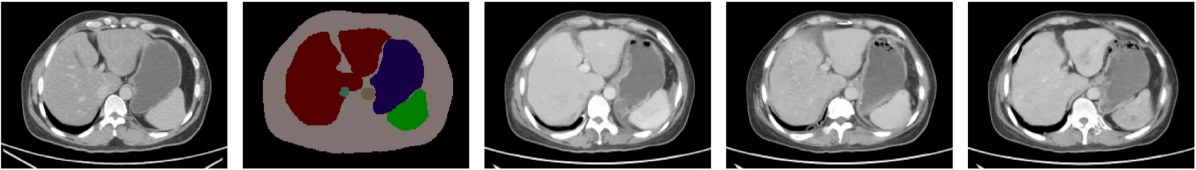

Comparison study. We carried out a quantitative evaluation of the diffusion models against other SOTA algorithms such as Pix2Pix, OASIS, SPADE, and SDM methods. In terms of image quality metrics such as FID, PSNR, and SSIM, the diffusion models outperformed non-diffusion-based methods. However, in terms of learned correspondence metrics like DSC, diffusion models surpassed other models for larger organs such as the liver, spleen, and kidneys. The OASIS method achieved superior performance for relatively small organs and structures like gallbladder and left adrenal gland. This may be because OASIS was good at synthesizing the clear boundary between small organs and the background, resulting in better segmentation results by TS and thus having higher DSC scores. Fig. 4 presents multiple results ranging from the lower to the upper abdomen, from different methods. It is worth noting that from the top row of Fig. 4 GAN-based methods struggled to synthesize images when the number of mask classes was sparse. For example, Pix2Pix and SPADE were unable to generate realistic images. OASIS generated an image from the upper abdomen, which was inconsistent with the location of the given mask. The bottom row illustrated the same trend. GAN-based models failed to synthesize the context information within the body mask, for example, the heart and lung. On the contrary, diffusion models including the SDM model succeed to generate reasonable images based on the given masks. One explanation was that diffusion models were more effective when the number of masks decreased and the corresponding supervision became sparser.

Figure 4: Results from different semantic image synthesis methods. The color map for different organs: body (beige), spleen (green), liver (dark red), right kidney (blue), left kidney (yellow), stomach (indigo), aorta (light brown), duodenum (light purple), pancreas (gray), right/left adrenal gland (dark/light green), inferior vena cava (aqua blue green), bladder (shallow brown), prostate (purple).